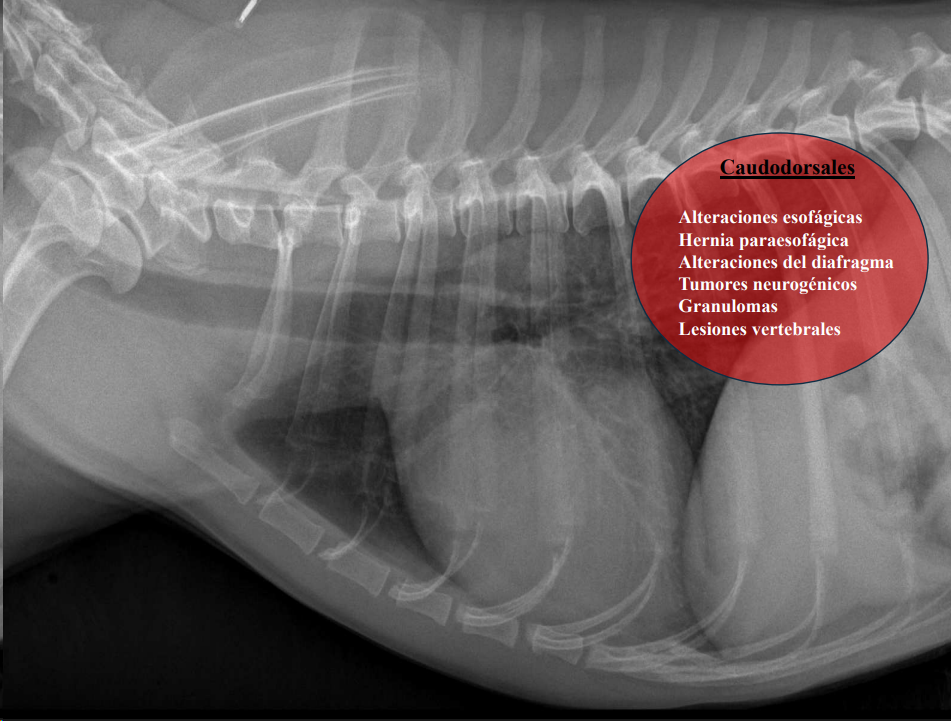

Caudodorsales: hernia paraesofágica, tumores neurogénicos, granulomas.

- Masas mediastínicas (craneodorsales, hilares, caudodorsales, caudoventrales, craneoventrales).

- Linfomas en gato, timomas en perros.